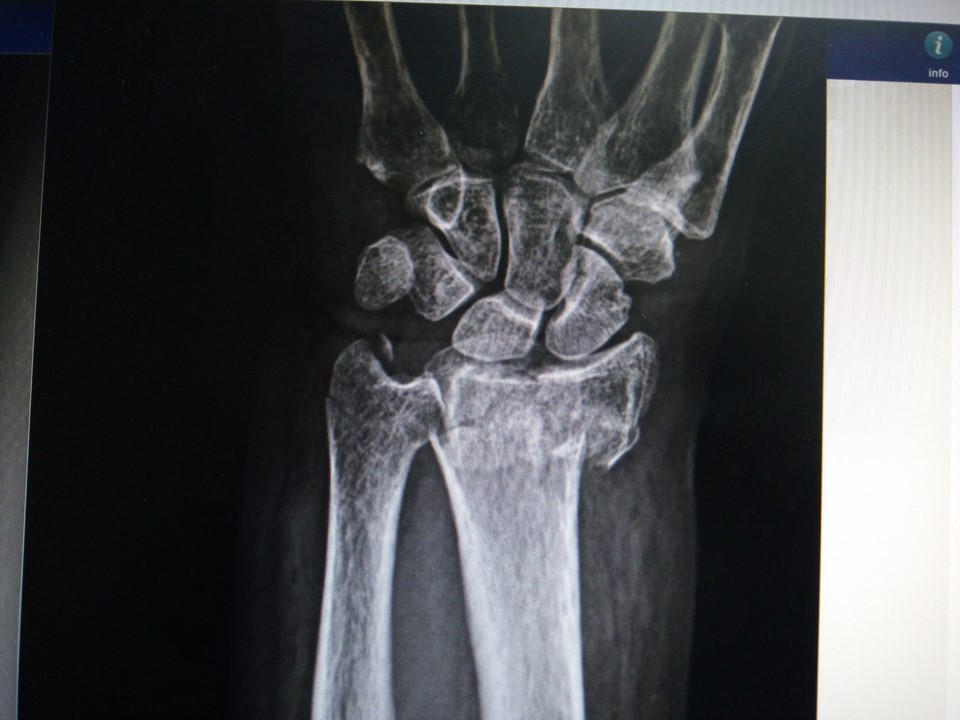

Al evaluar su muñeca izquierda pude notar que tenia mucho aumento de volumen y apenas la toque el dolor se noto inmediatamente con un enorme grito que casi me deja sordo, por lo cual le dije a la residente que la llevara a hacer unas radiografías de esa muñeca que lucía algo fea.

Al ver las radiografías enseguida se hizo notar una horrible fractura de la porción mas distal del radio izquierdo, en vista de los hallazgos no había más opción que levarla a quirófano para reducir la fractura.

Y así mismo sucedió, la señora Cecilia subió a quirófano y una hora después yo con mi equipo subimos a realizar la cirugía más fea del día, donde pudimos realizar la reducción de la fractura y la estabilizamos con un tutor externo para muñeca, lo cual consiste en una serie de clavos, tuercas, rotulas y barras.